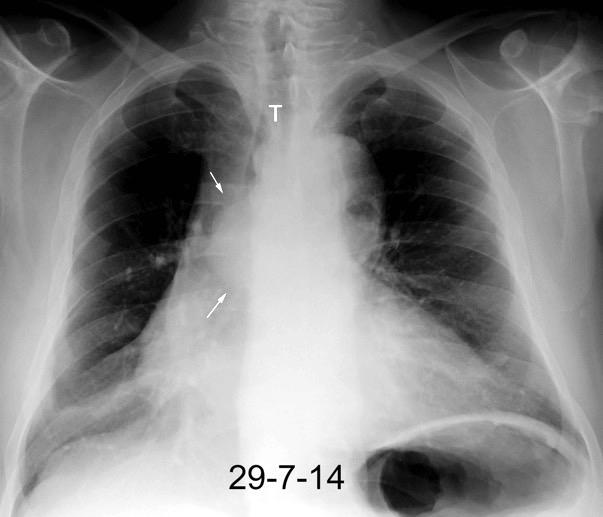

69. DESVIACIÓN TRAQUEAL A LA IZQUIERDA

71. DESVIACIÓN TRAQUEAL A LA DERECHA

73. DESVIACIÓN TRAQUEAL POSTERIOR